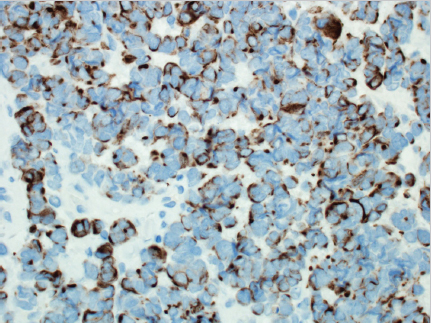

Fig. 5.2a, b). Immunohistochemistry must be completed to confirm the diagnosis, since metastatic small cell lung carcinoma (SCLC) can be indistinguishable on H&E. Cytokeratin-20 (CK-20) is found in 89 to 100% in cases of Merkel cell carcinoma, and is uncommonly seen in SCLC (

Fig. 5.3). Merkel cell carcinoma stains are positive for neuro-filaments in most cases, but SCLC stains are not. Conversely, thyroid transcription factor 1 is positive in most SCLCs, but it is seen rarely in Merkel cell carcinoma.8 For lesions that test equivocally, additional stains including chromogranin, synaptophysin, CD56, and neuron-specific enolase may be used to evaluate for other diagnoses.9